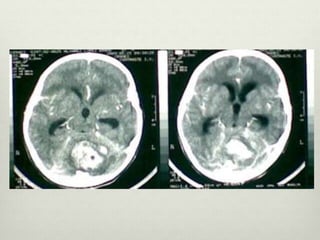

Tomografía

• Hiperdensa , bien definida vermiana o en hemisferio

cerebeloso

• Edema vasogénico

• Compresion IV Ventriculo

• Evidencia de la hidrocefalia

• Realce de contraste homogéneo

• La formación de quistes ( 59 % de los

casos)

• La calcificación - infrecuente

Tomografía • Hiperdensa ,bien definida vermiana o en hemisferio cerebeloso • Edema vasogénico • Compresion IV Ventriculo • Evidencia de la hidrocefalia • Realce de contraste homogéneo • La formación de quistes ( 59 % de los casos) • La calcificación - infrecuente